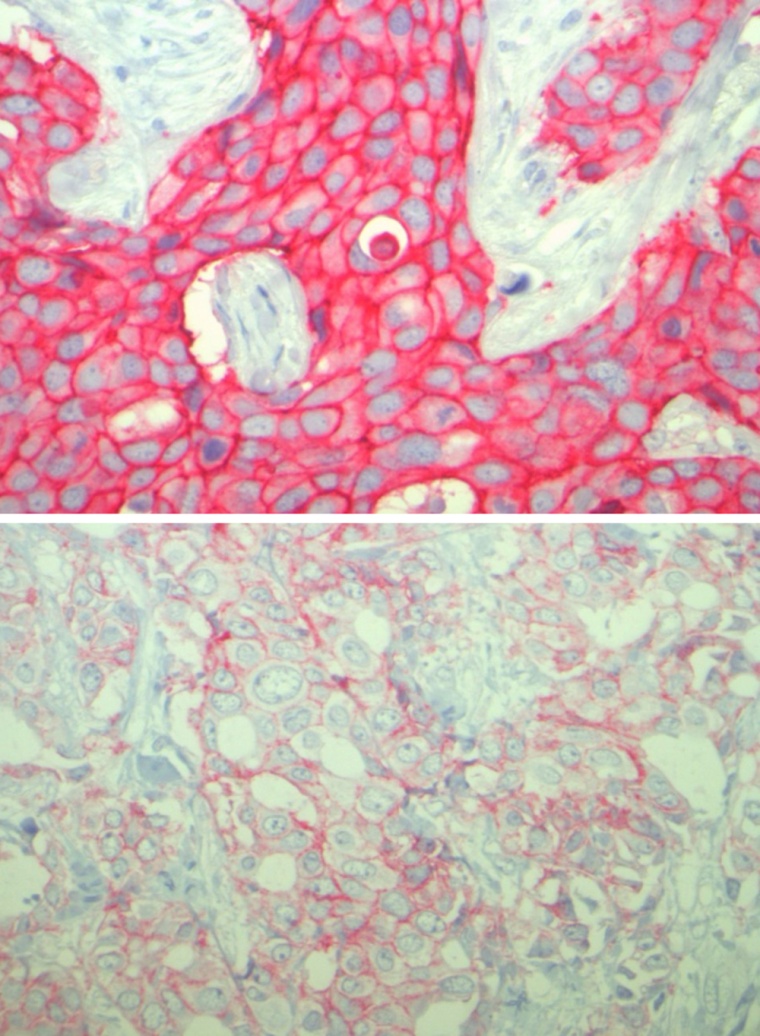

Bislang galt eine zielgerichtete Therapie nur dann als erfolgversprechend, wenn der Tumor eine sehr stark erhöhte Konzentration von HER2 aufweist. Das Forschungsteam um Denkert und Loibl untersuchte Brustkrebsgewebe von 2.310 Patientinnen, die eine Kombinationschemotherapie erhalten hatten.

„In 48 % dieser Gewebeproben zeigen eine schwach-positive Konzentration von HER2“, berichtet Denkert. „Wie wir herausfanden, lässt sich Tumorgewebe mit schwacher Positivität für das HER2-Protein als eigener Brustkrebs-Subtyp charakterisieren, der sich von Tumoren unterscheidet, die gar kein HER2-Protein aufweisen.“ Das wirkt sich insbesondere auf das Überleben der Betroffenen aus: „Wenn im Tumor das HER2-Protein in geringer Konzentration vorliegt, ist die Überlebenswahrscheinlichkeit der Betroffenen größer, als wenn das Gewebe gar kein HER2 enthält“, legt Loibl dar.